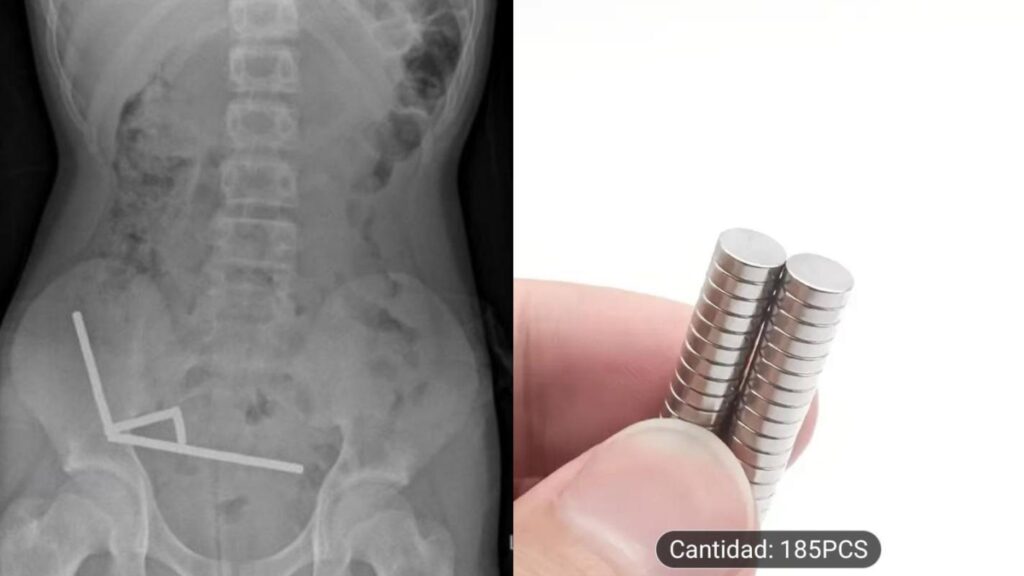

En el análisis físico, presentaba alta sensibilidad en el cuadrante inferior derecho de su abdomen, lo que fue confirmado por la radiografía abdominal, que reveló “cuatro cadenas lineales de imanes localizadas en el cuadrante inferior derecho del abdomen. Estas parecían ser partes separadas del intestino adheridas entre sí debido a las fuerzas magnéticas”.

Radiografía del niño que tragó los imanes (NZ Medical Journal)

En la consulta, el niño de 13 años confesó que se había tragado entre 80 a 100 imanes de alta potencia (neodimio) de 5x2mm que había comprado por el comercio online Temu.

Este tipo de imanes suele ser vendido en packs – Foto Temu